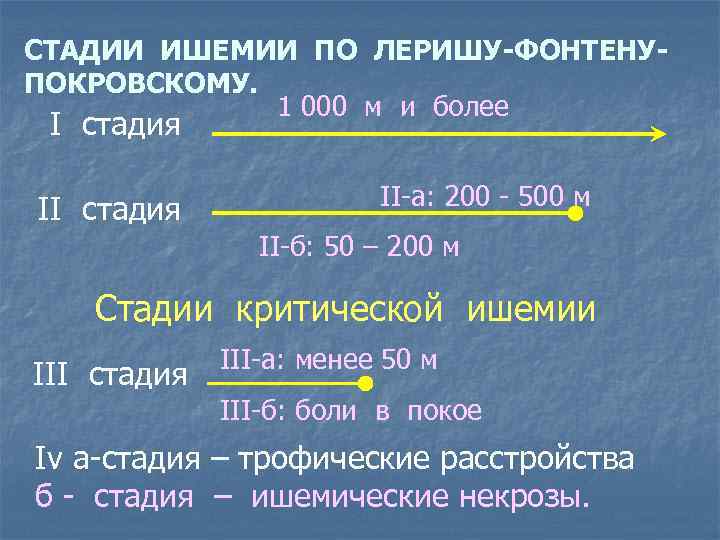

СТАДИИ ИШЕМИИ ПО ЛЕРИШУ-ФОНТЕНУПОКРОВСКОМУ. 1 000 м и более I стадия II-а: 200 - 500 м II-б: 50 – 200 м Стадии критической ишемии III стадия III-а: менее 50 м III-б: боли в покое Iv а-стадия – трофические расстройства б - стадия – ишемические некрозы.